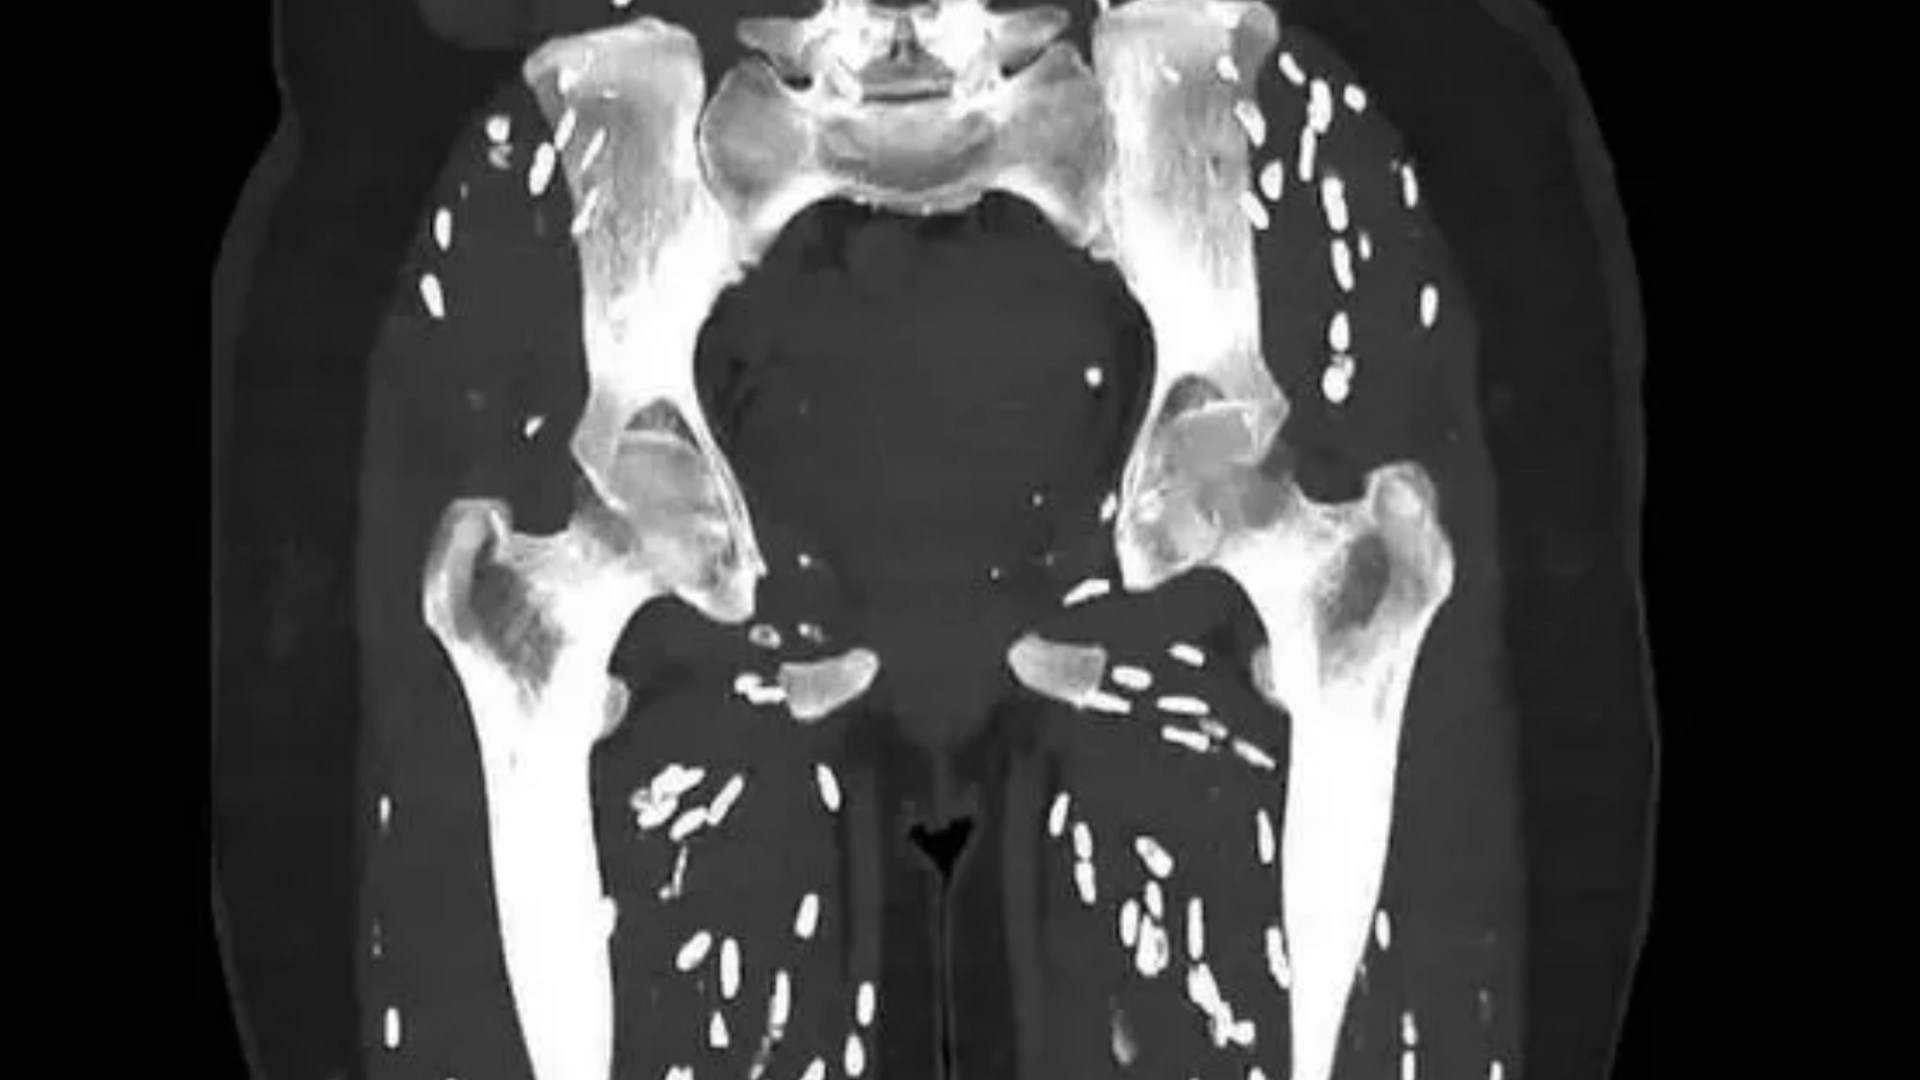

A DISTURBING scan described by a doctor as the “craziest” he’s ever seen highlights why you should always give your hands a good wash after going to the toilet.

It shows the lower body of a patient, which is riddled with rice grain-like pinpricks – a telltale sign of a nasty parasitic infection that can spread to the brain, eyes or muscles.

The doctor revealed that the patient in question was suffering from parasitic infection called cysticercosis.

It’s an infection caused by the larvae of the parasite Taenia solium, which occurs after a person swallows tapeworm eggs.

The body’s immune system typically kills offthe cysts, which calcify and form “rice grain”-like nodules that are visible in the scan.